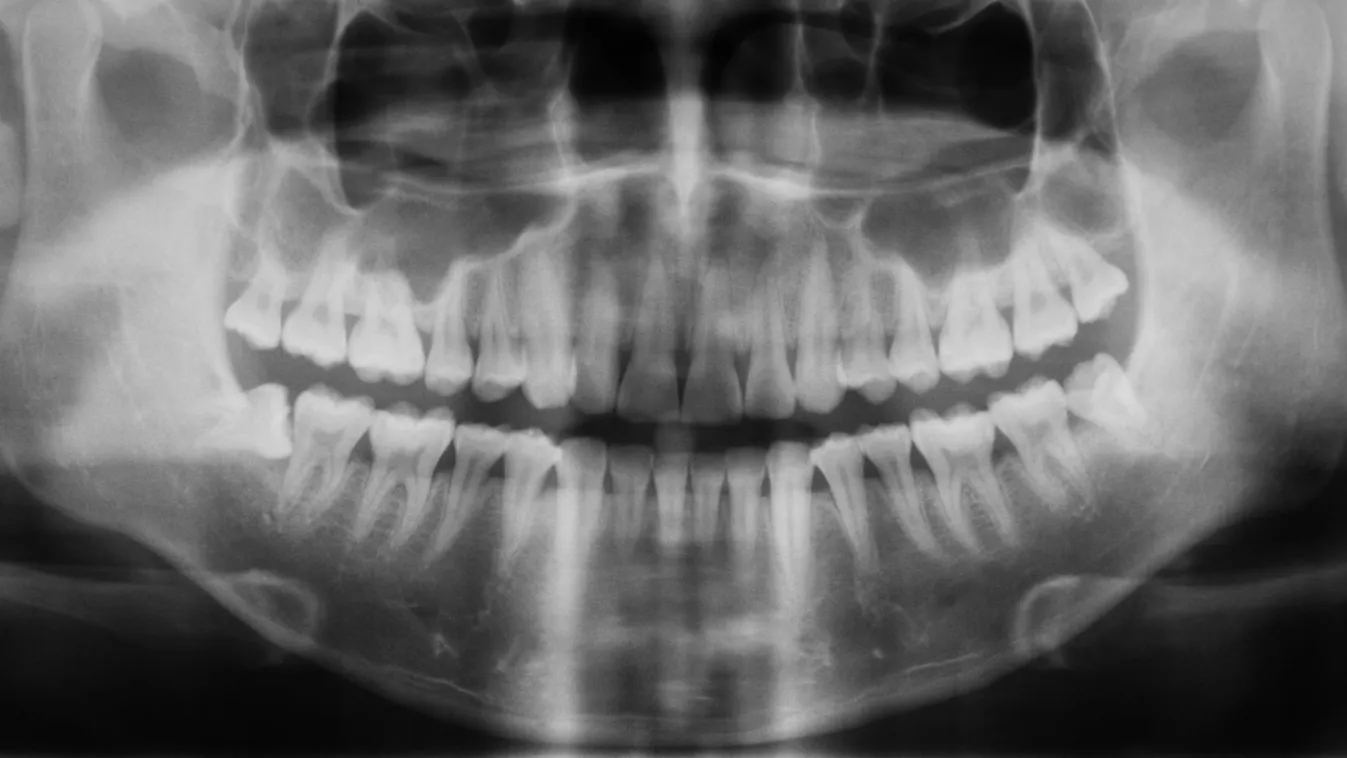

„A múlt héten egy egyszerű gyökérkezelésre számítottam, de a fogorvos a panorámaröntgen elkészítése után közölte, hogy a felvételen egy olyan kiterjedt gyulladás látható, hogy az őrlőfog már menthetetlen, mi több, veszélyezteti az épeket is. Nem volt sok időm gondolkodni, és az orvos szakértelmében bízva elfogadtam a javaslatát, így beleegyeztem a húzásba” – mondta a lapnak Sándor, aki kapott két érzéstelenítő injekciót, majd kiküldték várakozni, amíg a szer kifejti hatását. Miután egy másik pácienst elláttak, az asszisztens szólt a férfinak, hogy visszamehet. A beteg tehát ismét beült a fogorvosi székbe, nagyra tátotta a száját, majd a doktornő egy fogóval feszegetni kezdte a beteg fogat, ami a vártnál nehezebben lazult. A beavatkozás már bő húsz perce tartott, amikor az orvos egy határozottabb rántással megpróbálta a fogat eltávolítani.